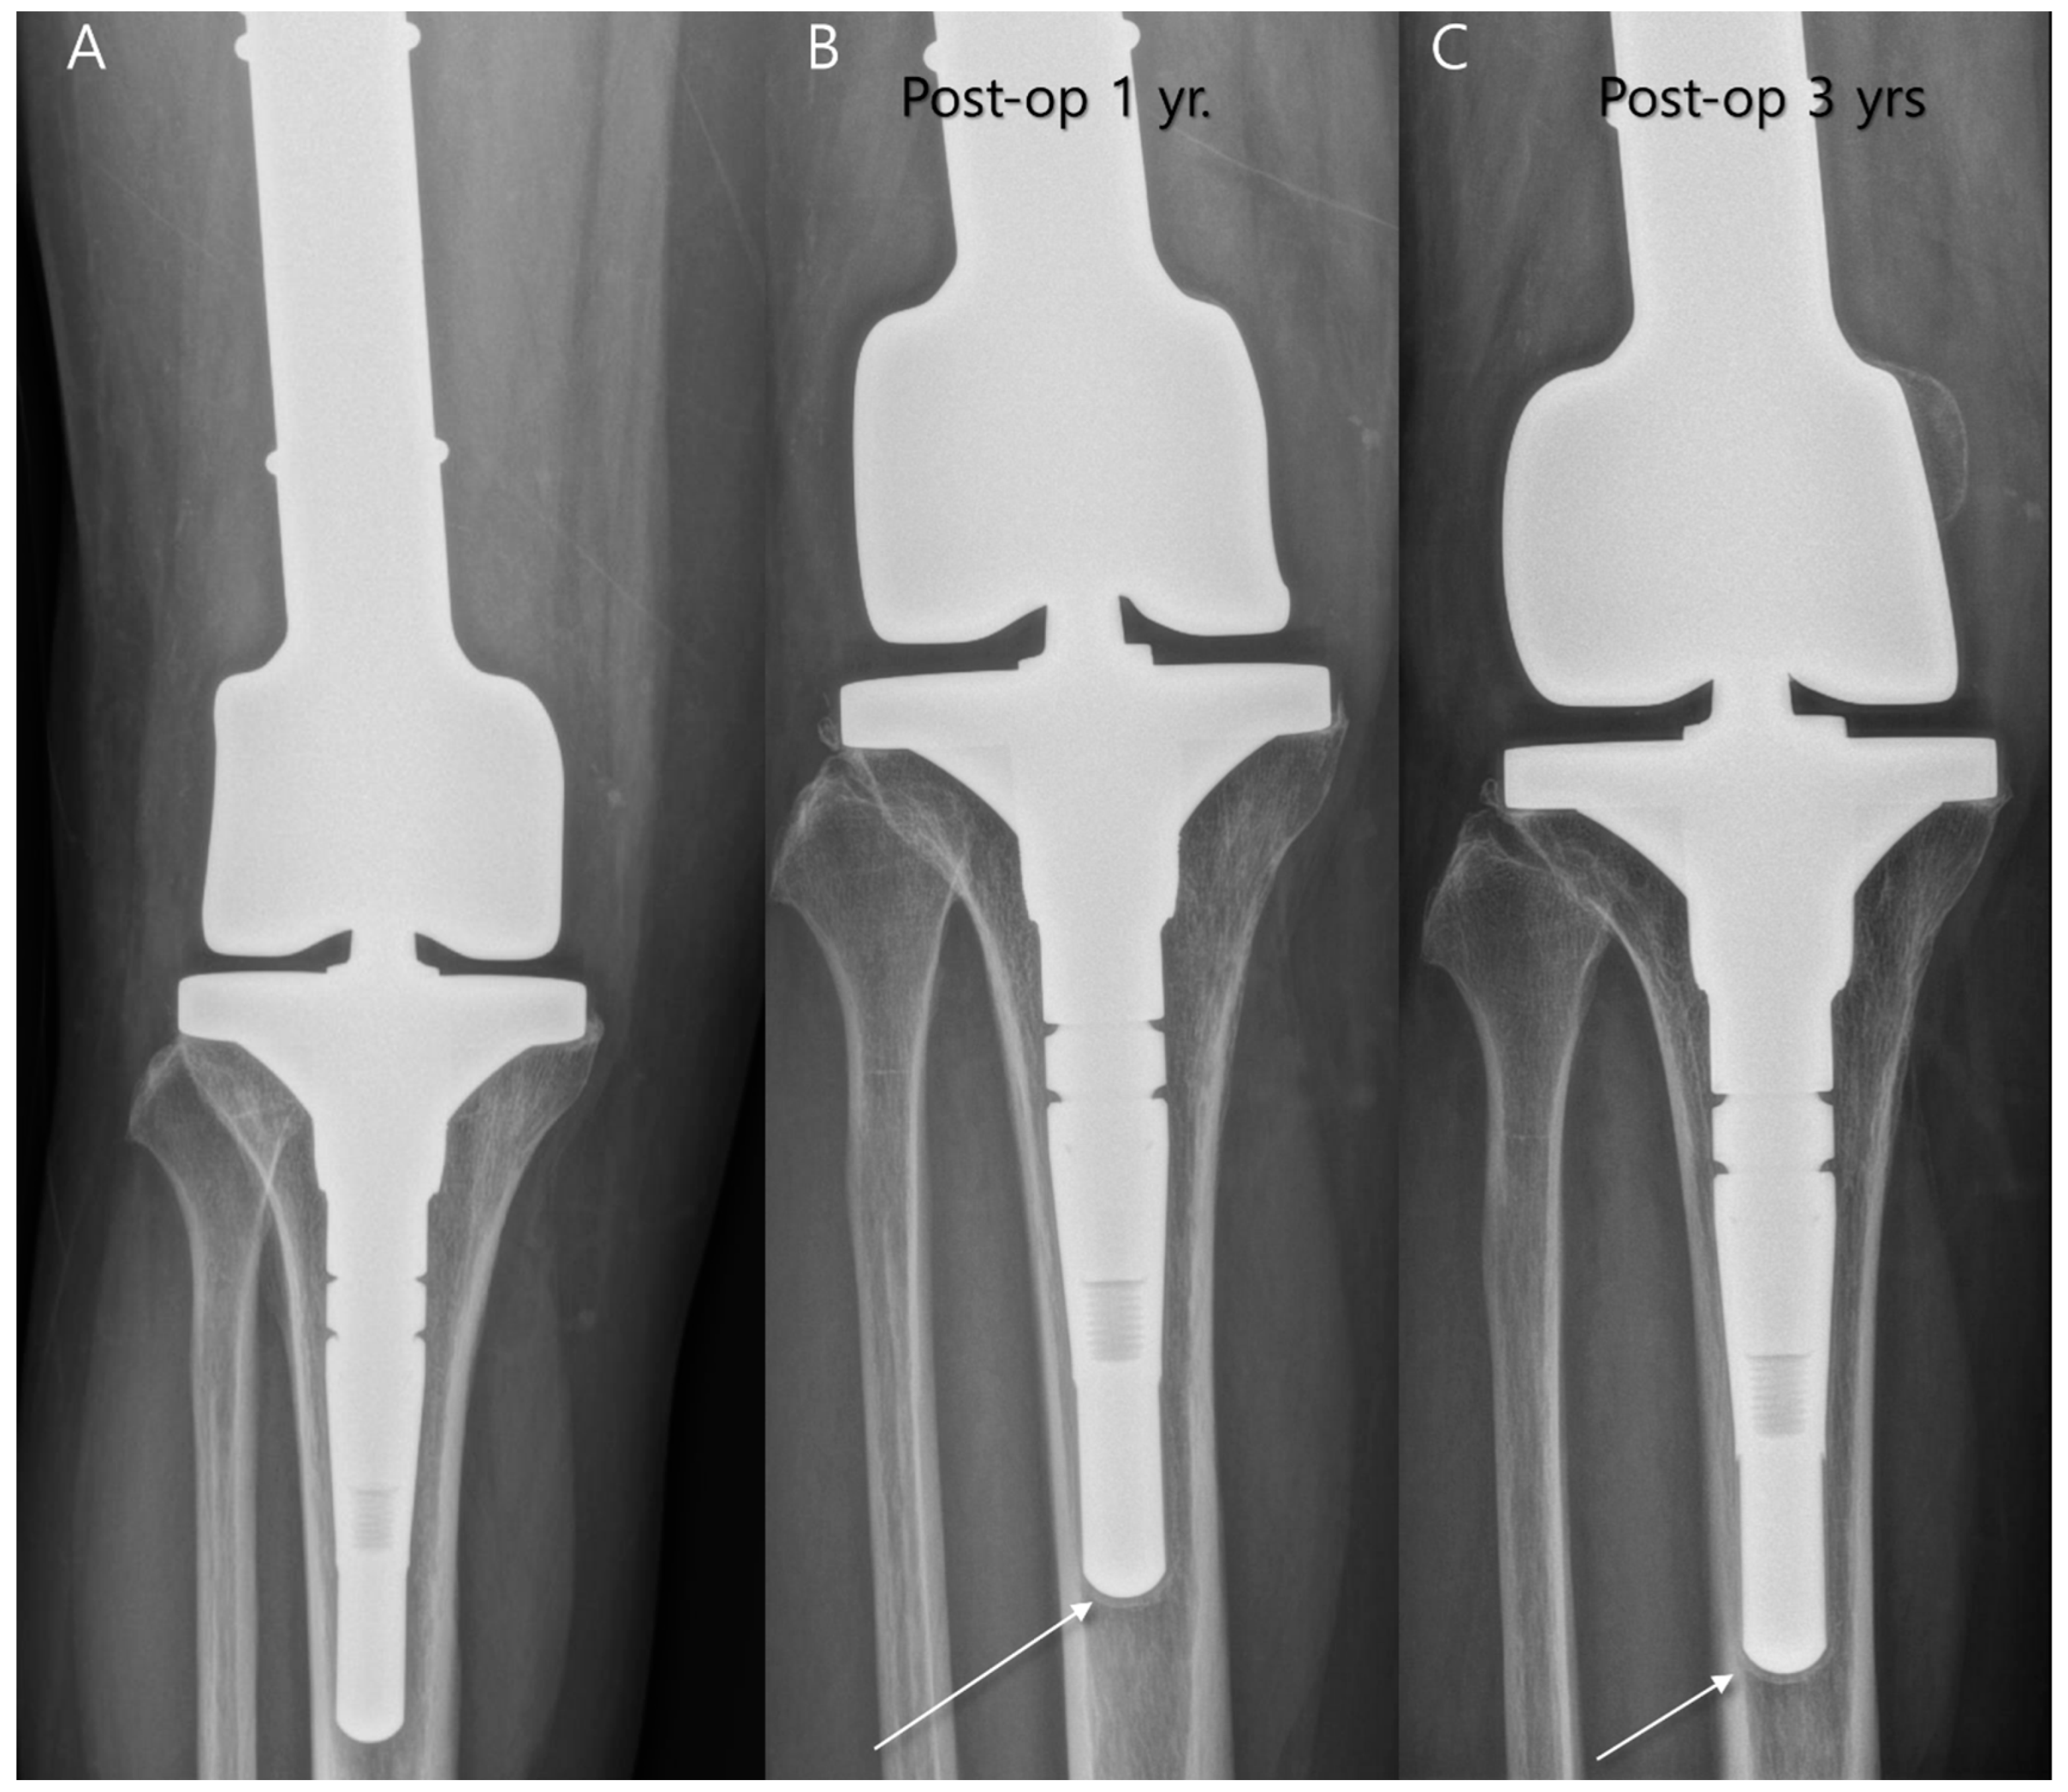

4.1. Postoperative Complication of Endoprostheses for Bone Tumors

4.1.2. Aseptic Loosening

4.1.3. Mechanical Failure

- Turcotte, R.E.; Stavropoulos, N.A.; Toreson, J.; Alsultan, M. Radiographic assessment of distal femur cemented stems in tumor endoprostheses. Eur. J. Orthop. Surg. Traumatol. 2017, 27, 821–827. [Google Scholar] [CrossRef]

- Henderson, E.R.; Groundland, J.S.; Pala, E.; Dennis, J.A.; Wooten, R.; Cheong, D.; Windhager, R.; Kotz, R.I.; Mercuri, M.; Funovics, P.T.; et al. Failure mode classification for tumor endoprostheses: Retrospective review of five institutions and a literature review. J. Bone Jt. Surg. 2011, 93, 418–429. [Google Scholar] [CrossRef]

- Shah, A.; Cardoso, F.N.; Souza, F.; Montreuil, J.; Pretell-Mazzini, J.; Temple, H.T.; Hornicek, F.; Crawford, B.; Subhawong, T.K. Failure Modes in Orthopedic Oncologic Reconstructive Surgery: A Review of Imaging Findings and Failure Rates. Curr. Oncol. 2024, 31, 6245–6266. [Google Scholar] [CrossRef]